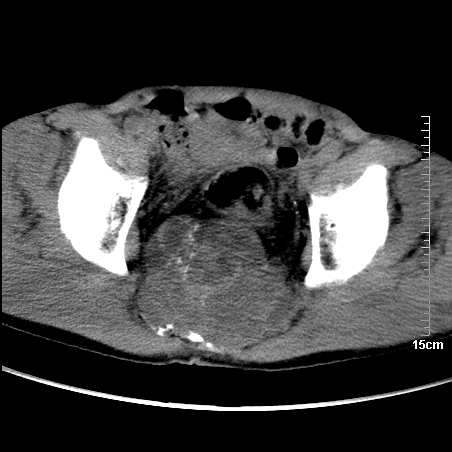

标题: CT16886:骶尾部占位:1.脊索瘤?2.巨细胞瘤?

增强:

1、骶尾部巨大软组织肿块,部分骶尾骨以被软组织肿块代替,呈不规则侵蚀;病变突向盆腔内;增强扫描病变呈不均质强化;首先考虑脊索瘤。不支持的一点就是病变内无钙化。

2、发生于骶尾椎者须与骨巨细胞瘤鉴别,骨巨细胞瘤一般发在上疗骶椎,肿瘤内无钙化,一般无侵袭性生长的表现。